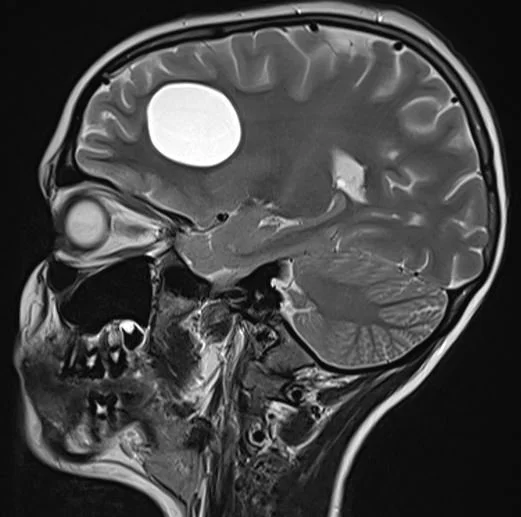

Rare and pediatric disease trials come with complex challenges that require specific expertise and experience. We have the radiology exerts to support the specific requirements of pediatric clinical trials. Many rare diseases affect children, and pediatric trials bring additional challenges.

They require specific protocols, involve additional regulations and demand expertise and experience. BICL’s experts are experienced in oncology, MSK and other pediatric disorders including growth plate disturbance, bone age and osteochondroma.